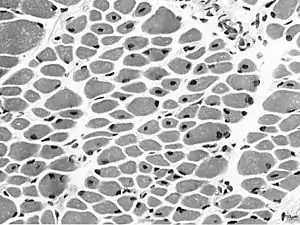

| Muscle biopsy from the quadriceps taken at 3 months of age from a girl with X-linked centronuclear ("myotubular") myopathy due to a mutation in the myotubularin (MTM1) gene and extremely skewed X-inactivation (H&E stain, transverse section). Note marked variability in fibre size, moderate increase in connective tissue and numerous central nuclei. | |

On examination of muscle biopsy material, the nuclear material is located predominantly in the center of the muscle cells, and is described as having any "myotubular" or "centronuclear" appearance. In terms of describing the muscle biopsy itself, "myotubular" or "centronuclear” are almost synonymous, and both terms point to the similar cellular-appearance among MTM and CNM. Thus, pathologists and treating physicians use those terms almost interchangeably, although researchers and clinicians are increasingly distinguishing between those phrases.

In general, a clinical myopathy and a muscle biopsy showing a centronuclear (nucleus in the center of the muscle cell) appearance would indicate a centronuclear myopathy (CNM). The most commonly diagnosed CNM is myotubular myopathy (MTM). However, muscle biopsy analysis alone cannot reliably distinguish myotubular myopathy from other forms of centronuclear myopathies, and thus genetic testing is required.Diagnostic workup is often coordinated by a treating neurologist. In the United States, care is often coordinated through clinics affiliated with the Muscular Dystrophy Association.